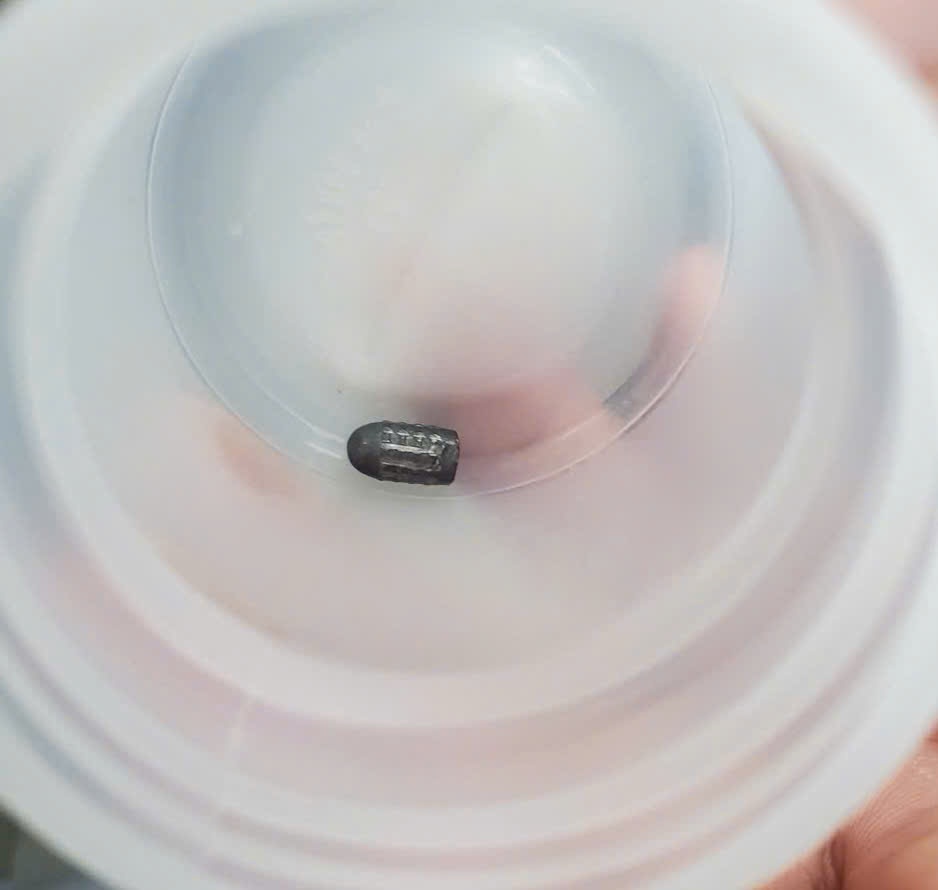

Phẫu thuật thành công một phụ nữ ở Cần Thơ bị đạn lạc trúng đầu khi đang làm vườn